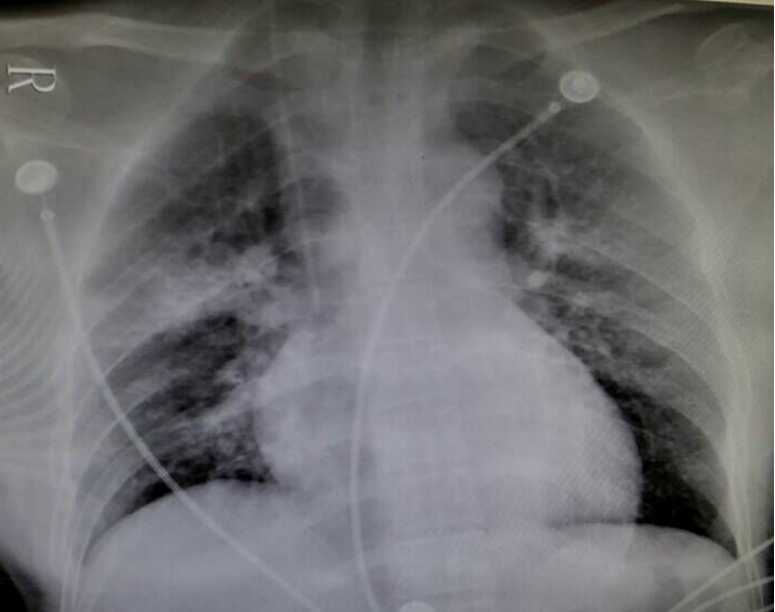

盐酸作用于人体组织使蛋白质凝固而发生坏死,组织细胞破坏,造成局部腐蚀性变化,表现为局部组织充血、水肿、坏死和溃疡,甚至空腔脏器穿孔,形成疤痕、狭窄和变形。口服洁厕灵者以消化道粘膜化学性灼伤、腐蚀、出血、甚至穿孔,同时伴有机体酸碱失衡。随着毒物吸收入血,可引起内脏器官的损害,以肝、肾功能受损较重。另外,在服用洁厕灵后,因腹部不适引起呕吐者有导致误吸的风险。有研究报道,洁厕灵中毒可导致急性肺损伤,呼吸衰竭。其作用机制为一方面洁厕灵吸入肺后,引起肺泡损伤,使其通透性增加,渗出增加,血液及淋巴回流受阻,从而发生急性肺水肿导致呼吸衰竭;另一方面洁厕灵可对咽喉部造成灼伤,引起咽喉部感染、肿胀、狭窄,从而导致大气道梗阻,反复肺部感染是造成呼吸衰竭的另一个主要的原因。此外还有误服洁厕灵后出现急性血管内溶血的报道。其可能的机制为酸中毒导致红细胞膜脆性增加而破坏,以及毒物吸收入血直接作用红细胞导致裂解。